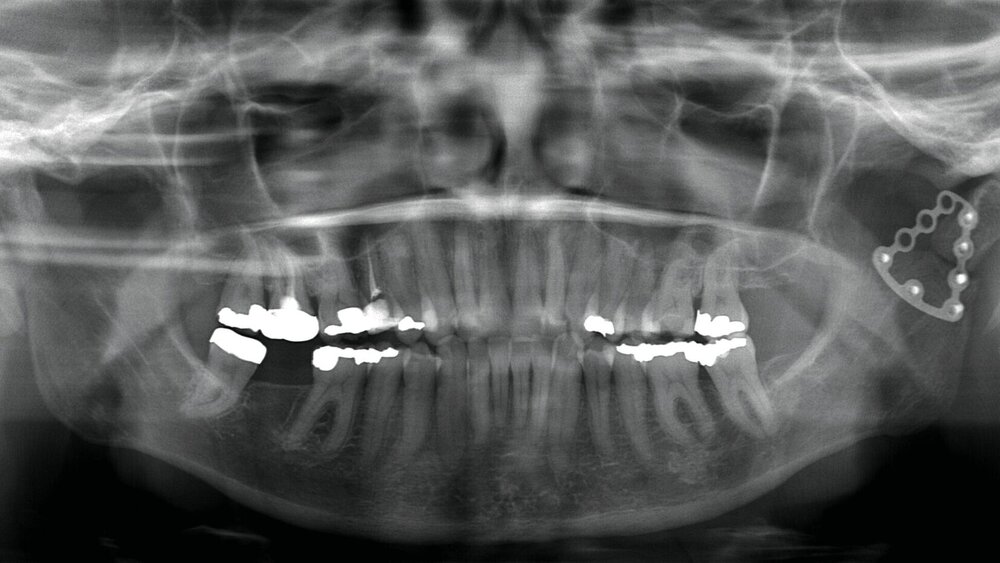

Anamnestisch waren bei ihr im März 2021 eine beidseitige Collumfraktur mit begleitendem frontoffenem Biss und eine Corpusfraktur im Unterkiefer infolge eines synkopalen Sturzes nach einer COVID-19-Impfung aufgetreten. Da das linke Collum in Fehlstellung verheilte, erfolgte alio loco eine operative Revision mit Osteosynthese (Abbildung 1). Das Metall wurde im April 2022 entfernt. Der Hauszahnarzt führte daraufhin im Verlauf eine Aligner-Therapie durch, um die immer noch fehlerhafte Okklusion zu optimieren sowie diverse Dreh- und Kippstände zu beseitigen.

Klinisch zeigten sich diverse großflächig, mehrheitlich mit Amalgam gefüllte Seitenzähne, suffiziente endodontische Behandlungen an den Zähnen 16 und 14 sowie intakte Kronen an den Zähnen 16 und 48 (Abbildung 2). Ein Parodontaler Screening-Index (PSI) wurde erhoben (1-1-0-0-2-1), der stabile Verhältnisse nachwies. Das funktionelle CMD-Screening zeigte eine nicht-druckdolente Kaumuskulatur sowie eine uneingeschränkte Mundöffnung ohne Reiben und Knacken.